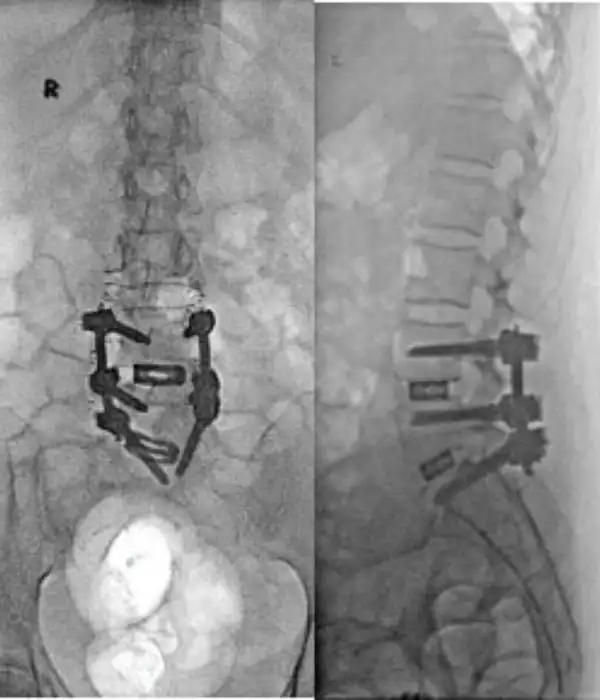

Degen Scoliosis Post operative Xray